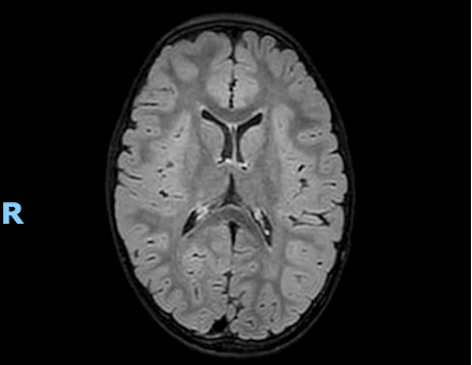

Per il quadro neurologico si richiede RM che evidenzia quadro di leucoencefalopatia con ipotrofia cerebrale (Figura 2). Dallapprofondimento anamnestico emerge che la bambina segue una dieta vegana e non ha mai eseguito integrazione vitaminica, dato confermato dal sopraggiunto valore di vitamina B12 (100 pg/ml, VN 191-663 pg/ml).

In entrambi i casi, dopo iniziale supporto trasfusionale, la supplementazione con idrossicobalamina ha determinato il progressivo miglioramento clinico e la risoluzione della citopenia (Figura 3).